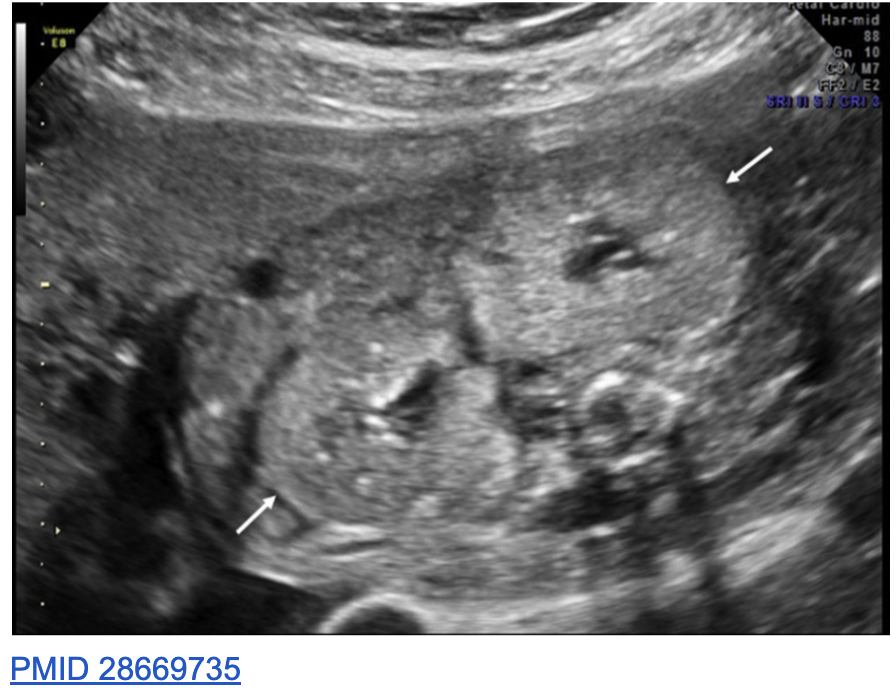

6/ Prenatal imaging of ARPKD on ultrasound shows

🔷Bilateral enlarged kidneys with loss of corticomedullary differentiation,

🔷Subcortical hypo echoic rim with predominantly medullary cysts- “Snow Storm” appearance.

🔷Oligohydramnios and absence of urine in the bladder.

📌Ultrasound shows enlarged kidneys with multiple tiny cysts of diameter < 3mm.

📌High-resolution ultrasonography shows medullary ductal dilations where medullary cysts are predominantly present.

PMID 20413436